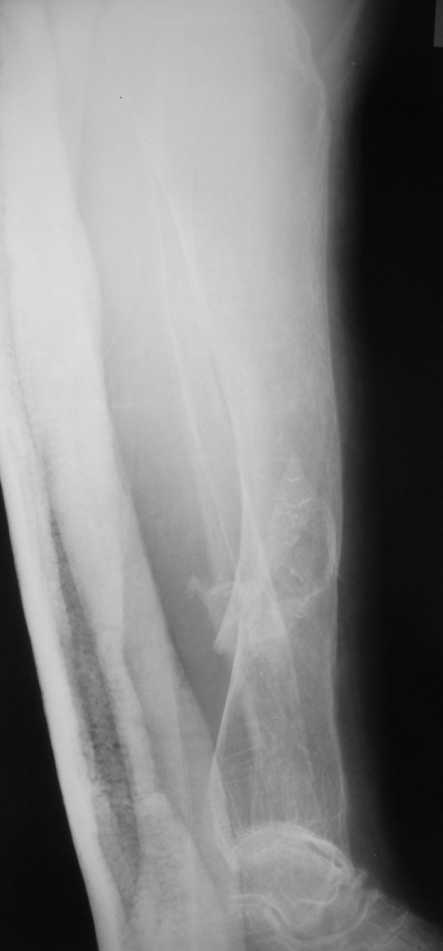

Контрольные рентгенограммы прилагаю.

Проблема в том, что в сагитальной плоскости угол голеней =30 градусам. Ширина канала 30.

ДС> Проблема в том, что в сагитальной плоскости угол голеней =30 градусам. Ширина канала 30.

Если при введении стержня будет видно, что из-за искривления дело идет к перфорации стенки, надо будет сделать чрескожную остеотомию на уровне кончика стержня.

Судя по Ro-граммах у больной скорее всего Vit-D

резистентный рахит и его последствия.Имеем наблюдения лечения остеопороза у данного контингента больных активными формами Vit-D -кальцитриол,даже в таком возрасте (положытельные результаты уже через 1-2 мес.).Фиксация фрагментов возможна внеочеговым аппаратом (самонарезные стержни в аппарате Илизарова).